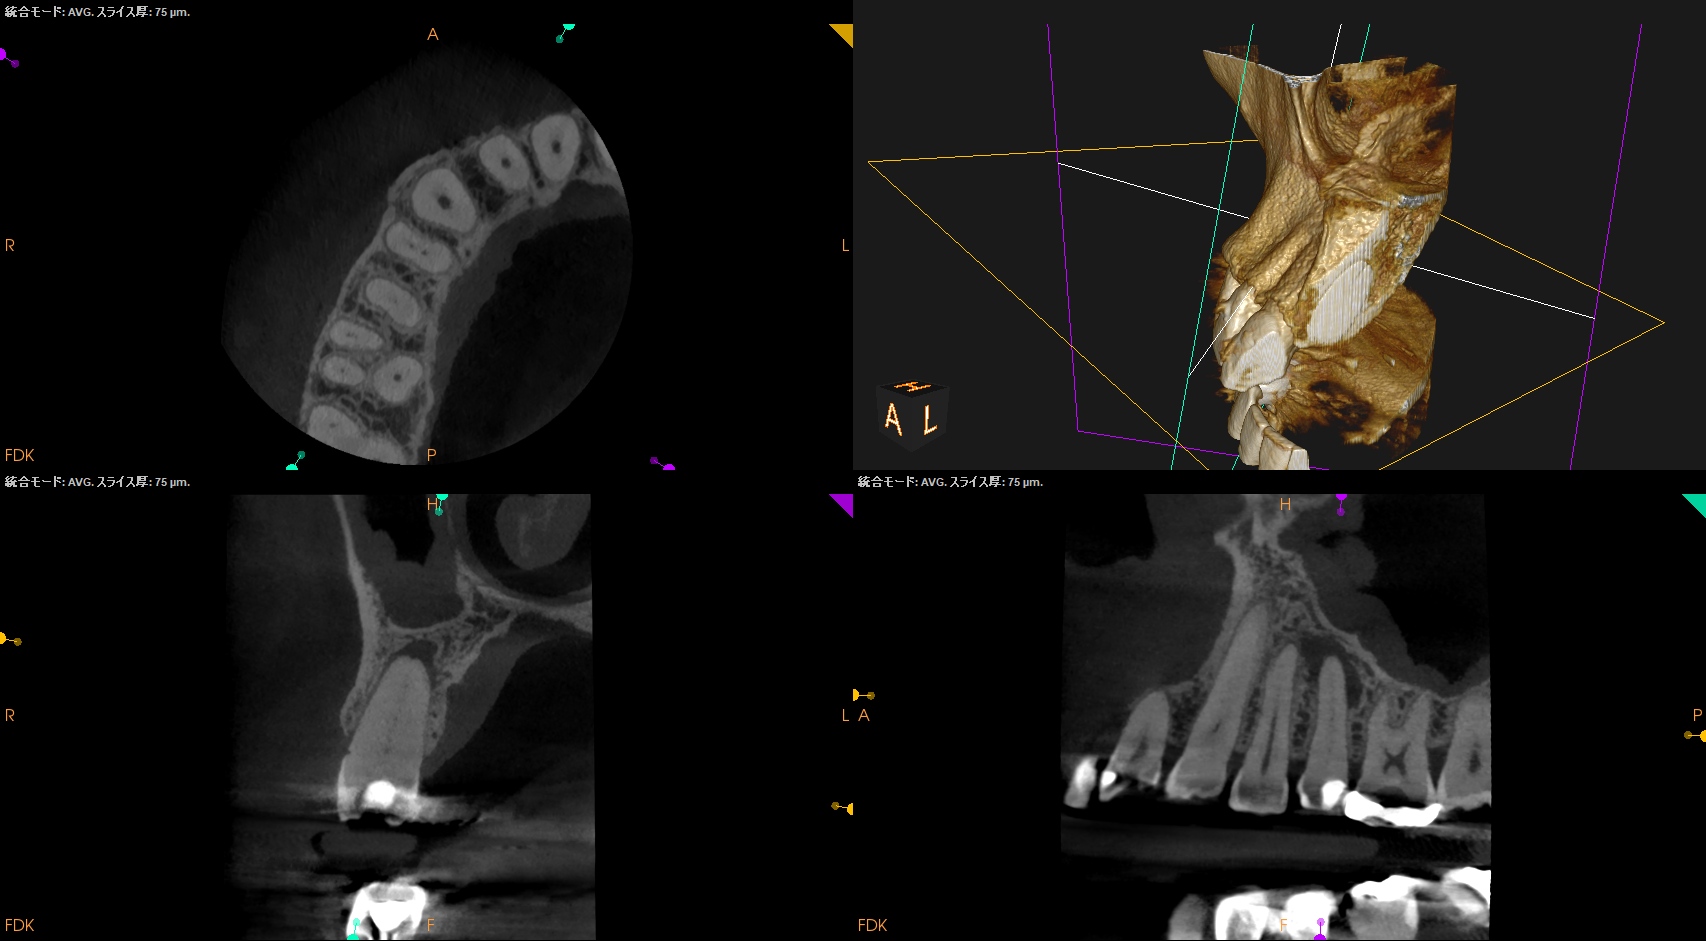

#4 RCT(2025.5.28)

生活歯髄療法で根管が石灰化していたため、#17の短針でスカウティングしている。

成人の生活歯髄療法の負の側面が顔を出した瞬間だ。

C+ File #10→8→6→K File #10→#8で根管が穿通した。

#8で穿通したと言うことは、

Apical Foramenが#8である。

そこから0.5mm上部は#9であるので、いわゆるグライドパスが必要な状態になる。

したがって、K Fileを1mm突き出した。

するとForamenが#10であるのでそこから0.5mm上部が#11であるのでグライドパスが不要である。

このように現代の歯内療法はいかにそれを避けて根管形成するか?が全てであろう。

湾曲根管ではないが、石灰化根管であるので#20.05からスタートした。

次が#25.Vで、壊死歯髄であるので#40.04まで根管形成した。

#35.04で根管充填した。

作業内容は以下である。

PA,CBCTを術後に撮影した。

問題はないだろう。